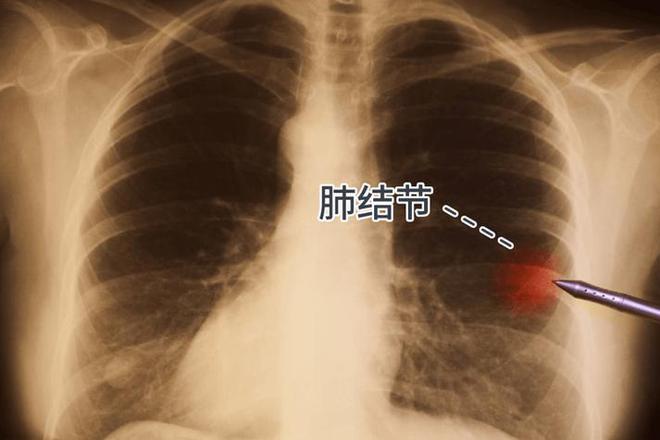

肺结核,这个听起来就让人心头一颤的疾病,它真的严重吗?让我告诉你,它不仅仅是一种病,它是潜伏在空气中的幽灵,无声无息地侵蚀着我们的生命。

想象一下,一个本应充满活力的身体,突然间变得虚弱无力,那种从内而外的疲倦感,就像是生命力被一点点抽走。咳嗽成了日常,每一次呼吸都像是在与死神赛跑。这不是电影情节,这是真实的肺结核患者的生活写照。

更可怕的是,肺结核的传播悄无声息。一个不经意间的咳嗽,一个轻声的叹息,都可能将这个致命的疾病传递给他人。它不分年龄,不分性别,只要有空气的地方,就有它的身影。

但不要害怕,因为知识就是力量。了解肺结核,认识到它的严重性,我们才能更好地预防和治疗。记住,定期体检,保持健康的生活习惯,是对抗这个幽灵的最有效武器。